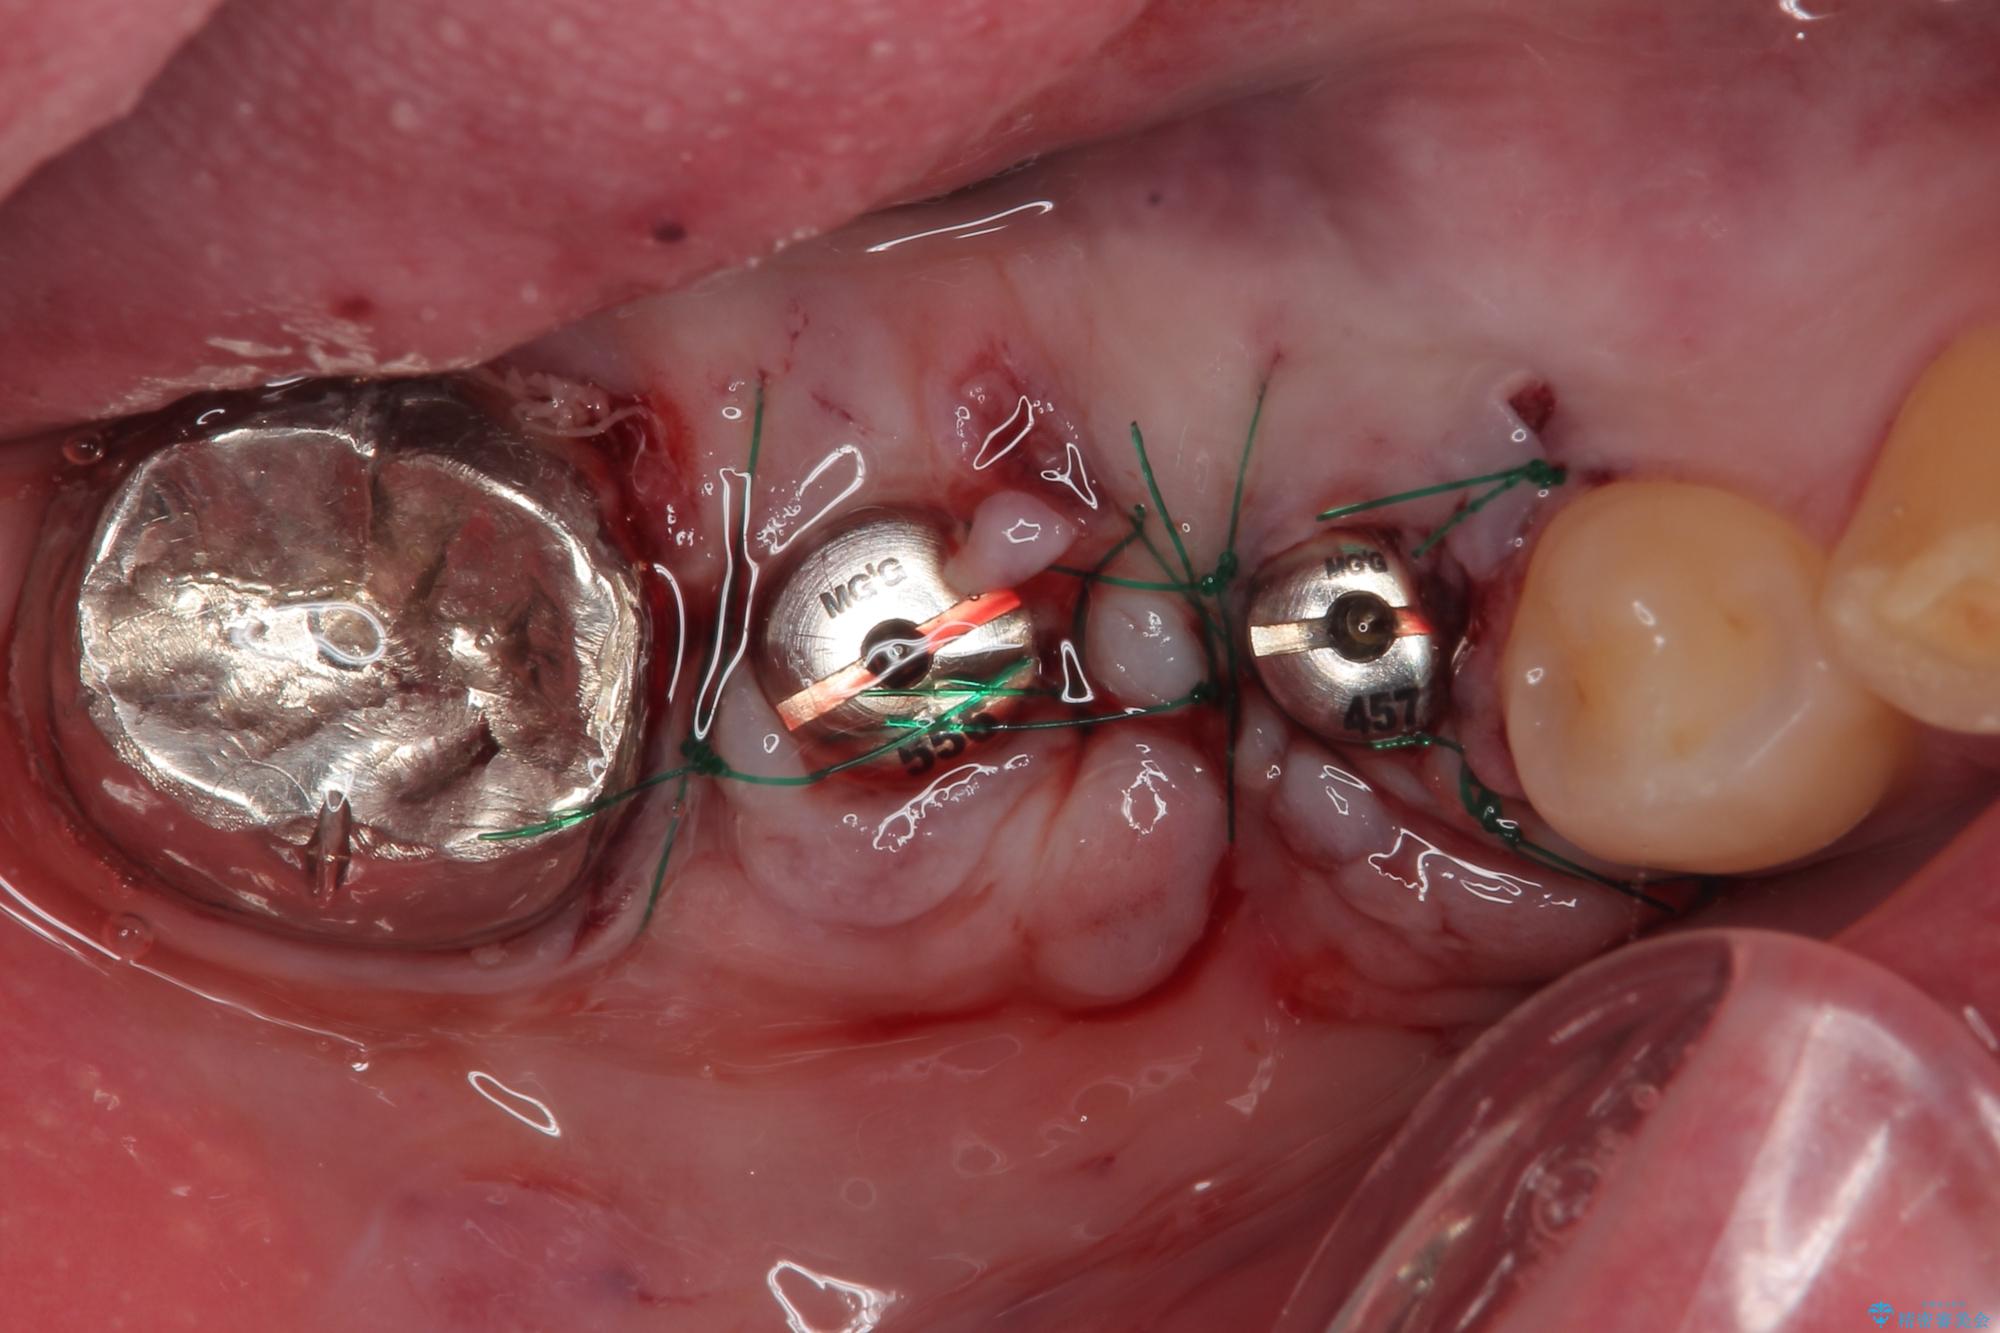

抜歯即時埋入部と後方の欠損部は、即日荷重(インプラント埋入と同時に仮歯を装着すること)が可能な安定値が得られましたが、長い期間欠損した状態で過ごすと、欠損部に舌を押し当てる癖が発現してしまい、舌からの側方圧でインプラントが脱離するリスクが著しく高まってしまうため、即日荷重は行いませんでした。

おかげでインプラントは無事に生着し、僅か4ヶ月で治療を終えることができました。